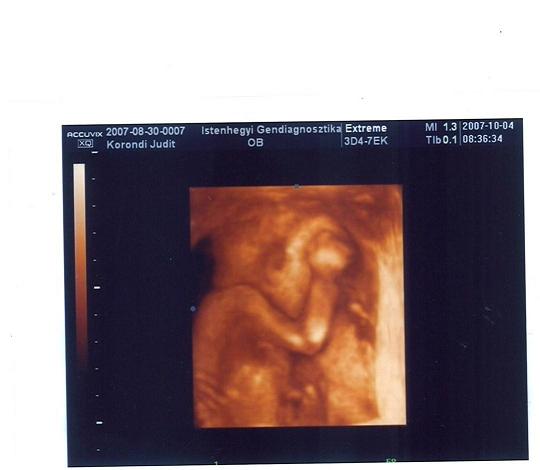

A Mátyásföldi UH-t az egyik kistarcsai doki csinálja, vérprofi és nagyon rendes. Évek óta csinálja, asszem egyébként ott ov. helyettes főorvos, csak basszus, nem jut eszembe a neve. Annak idején már Gordonról eszement jó képeket csinált, az akkori (5 évvel ezelőtti) kistarcsai gépekkel. Ha akarod, meg is keresem, az egyik a babaneten is fent van az albumomban, 9 hetes pocilakó Gordon picúrról, olyan, mint egy asztronauta, nagyon édi.

Szóljál, akkor megkeresem a linket. Mostanában többször láttam a tv-ben ultrahangos műsorokban előadóként, de szakmai körökben is nagy a respektje. Az egyedüli kérdés, hogy milyen profi géppel dolgoznak.